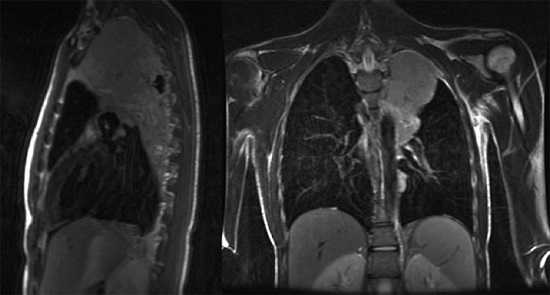

Что показывает МРТ органов грудной клетки

В грудной клетке расположено множество жизненно важных органов, патологии которых сложно диагностировать классическими способами: они скрыты за костями грудины, ребрами, позвоночником, мягкими тканями. Информативным способом, который способен показать структуру, а также функциональность органов, расположенных здесь, врачи называют МРТ — магнитно-резонансную томографию с контрастом или без него. Метод идеально подходит для исследования находящихся внутри грудины органов, сосудов, желез, лимфоузлов, но наиболее эффективным его считают в диагностике опухолевых процессов.

Какие органы проверяют на МРТ грудной клетки?

Чтобы понять, что показывает МРТ грудной клетки, важно понимать суть метода. Он состоит в способности мощного магнитного поля провоцировать резонанс молекул водорода, который в больших количествах содержится в органах грудной клетки (сокращенно ОГК). Магнитно-резонансный томограф улавливает резонансные колебания и отображает их на теле-экране в виде серии монохромных снимков, представляющих собой срезы обследуемой области определенной толщины: чем мощнее МР-аппарат, тем «тоньше» срезы и точнее результаты. Также на основе полученных данных можно сделать трехмерную модель любой структуры, находящейся в полости груди.